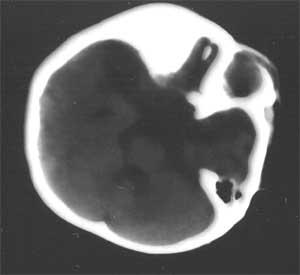

幕上幕下脑室、脑池、脑沟均见扩张积液,考虑脑发育不良。片子质量不好,前囟门似乎偏小,颅骨骨缝不知是否有闭合。9个月幼儿,头围应该不小于40厘米,请测量头围周径。应该没有胼胝体发育不良。至于“右侧基底节区缺血性改变”,片子质量差,看不清楚。

从ct片看1大脑纵裂增宽2侧脑室扩大3蛛网膜下腔增宽 应考虑1胼胝体发育不良,2脑发育不良或萎缩(两周前一般无临床意义应称蛛网膜下腔增宽或外周性脑积水)

不同意胼胝体发育不良的诊断,现在ct表现为脑沟、脑池增宽,双测额骨内板下方带状液体影,双测侧脑室略扩大,我认为应诊断为1、脑发育不全。2、外部性脑积水。情况应该很严重。

粗看:1。双侧额颞顶叶均有不同程度萎缩,脑实质变薄,2。脑室系统对称性扩张,大脑沟裂增宽变深。3。双基底节区未见明确低密灶,胼胝体发育良好。综上所述考虑有:1)大脑发育不良;2)严重脑缺血缺氧性脑病后遗症?个人意见仅供参考。

2 患儿有外部性脑积水,但其实质是蛛网膜下腔的增宽,为自愈性,无需处理,一般前囟闭合后便自行消失。ct表现为大脑纵裂和双额颞区蛛网膜下腔增宽,可有轻度的脑室系统扩张。

3 本例 患儿除外部性脑积水外的确有其他部位脑沟的增宽,尤以双顶叶为著,右侧基底节区可见低密度灶,以上可以为新生儿缺氧缺血性脑病所遗留,但并不严重,我想随着治疗锻炼患儿恢复应该会不错的。[em1][em4][em9][em14]

前纵裂池与三脑室相连,无明显侧脑室分离,可能胼胝体前部发育不全。两额顶部脑组织量减少,脑沟裂增宽,脑室扩大,肯定大脑发育不全,智力会受影响,现在该能看出来吧,孩子反应怎样。

片子比较暗。从这几张片子来看,大脑纵裂池似与侧脑室、三脑室交通,两侧额叶之间没有看到明显的脑白质交汇区(胼胝体膝部),如果是这样的话,应该考虑胼胝体发育不良。